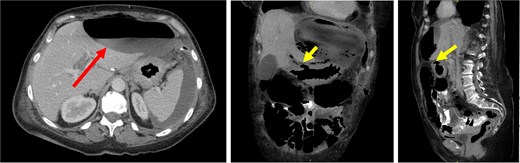

Postoperatively, the patient experienced persistent abdominal pain and rising inflammatory markers. Repeat CT showed an enlarging intra-abdominal collection suggestive of ongoing leakage (Fig. 2). She expressed a strong desire for life-saving treatment, despite her diagnosis of advanced metastatic disease. After extensive multidisciplinary discussion, an emergency open total gastrectomy with Roux-en-Y reconstruction was performed. This was undertaken with a palliative R1 resection intent. The operation was technically challenging because the stomach had extensive tumor invasion to the retroperitoneum, porta hepatis, as well as splenic hilum. Despite a difficult resection, the case progressed well. The resected specimen showed metastatic poorly differentiated diffuse gastric adenocarcinoma of breast origin with features of pleomorphic ILC, involving the proximal resection margin and four out of seven lymph nodes with metastatic carcinoma (Fig. 3).

CT images demonstrated a large, thin-walled anterior epigastric collection with an air-fluid level (long/red arrow) measuring 10.8 × 5.8 × 16.4 cm, positioned anterior to the left hepatic lobe and the gastric body. This collection appeared to communicate with the suspected perforation site (short/yellow arrows). Additionally, loculated fluid pockets were observed around the spleen and the left upper quadrant bowel loops, along with interspersed free fluid and gas locules likely leaking from the stomach.